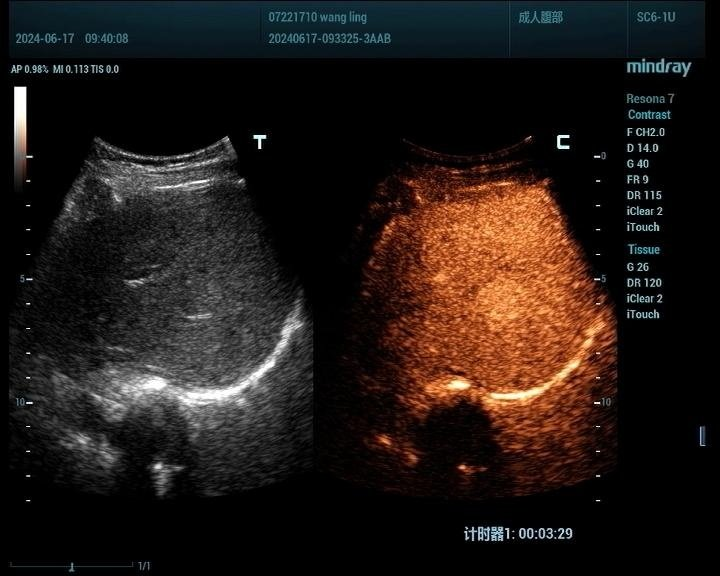

1、肝脏占位性病变:

肝脏肿瘤分为良性和恶性,其中血管瘤是最常见的肝脏良性肿瘤,肝癌是最常见的恶性肿瘤。肝脏肿瘤超声影像诊断方面主要有肿瘤病灶的检出、对已检测肿瘤的定性诊断、肝局灶性病灶中肿瘤与非肿瘤病变的鉴别。超声造影对肝脏肿瘤的鉴别诊断主要是通过增强和动态增强方式观察肿瘤。

肝癌病例1